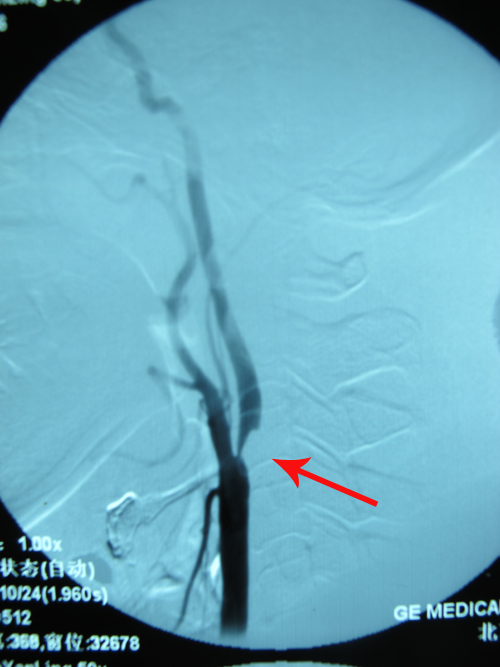

DSA示:右侧颈内动脉起始段90%狭窄,左侧颈内动脉管径全程较细,左侧大脑中动脉未显影,代之异常丰富毛细血管形成,右侧颈内动脉虹吸部异常 血管形成。